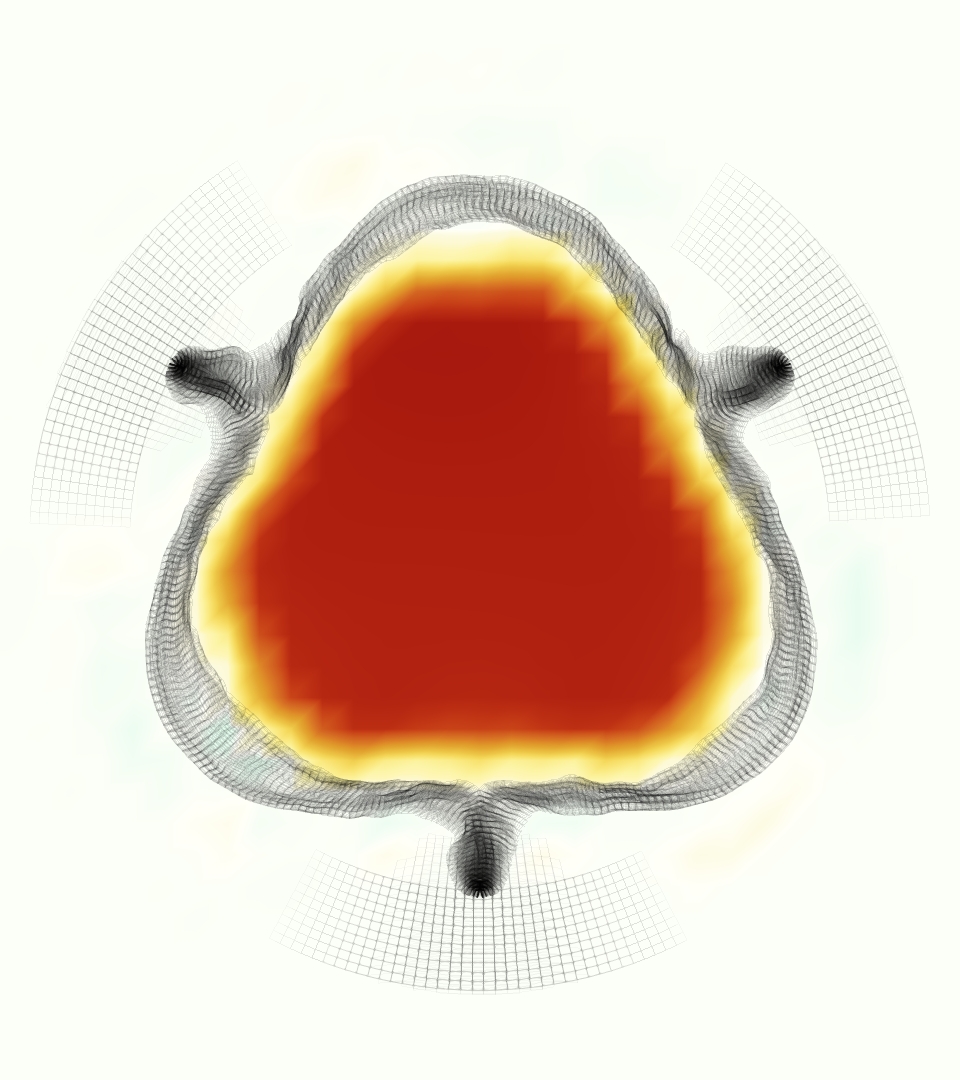

The gross morphology of the model valve that emerged from this process is shown in Figure 4. The free edge was 2.87 cm, corresponding to 3.3 cm in the predicted loaded configuration. After the pinching the leaflets together at the commissures, this left approximately 2.1 cm of free edge rest length per leaflet free to move independently of the other leaflets, within measurement error of ±0.1 cm from the free edge length of 2.2 cm measured on the prostheses. The leaflet rest height was 0.94 cm corresponding to a predicted loaded height of 1.44 cm. The measured leaflet height of 1.3 cm is nearly the predicted loaded height of 1.44 cm, which may be because the leaflets are so compliant in the radial direction, that pulling them flat to measure them achieved substantial stretches. The fiber orientation of the model runs from commissure to commissure and qualitatively matches experimental observations [38], though direct quantitative comparison is beyond the scope of this work. One minor limitation is that we do not add bending rigidity to the leaflets, beyond what emerges from the thickening process described above, and thus may not accurately capture leaflet flutter or other similar behaviors. Based on the thickness of mm, we estimated the mean tangent modulus at the predicted loaded stretches as dynes/cm2 circumferentially and dynes/cm2 radially. The prosthetic valve tissue is fixed in glutaraldehyde, and literature values for the fully-recruited circumferential tangent modulus of fixed porcine aortic valve tissue vary widely. Based on the experimental measurements of Billiar and Sacks and their constitutive law for valves fixed under 4 mmHg of pressure, we evaluated their constitutive law at the relevant stretches and and estimated the circumferential tangent modulus to be dynes/cm2 [6]. Rousseau et al. reported moduli ranging from to dynes/cm2, depending on the applied preload during fixation [36]. Sung et al. reported moduli ranging from to dynes/cm2, depending on fixation pressure [43]. Thus our estimated tangent modulus falls within the range of existing studies, so we considered our resultant modulus in good agreement given the complexity of the steps involved, phenomenological nature of the constitutive law and uncertainties in experiments. We do not have access to the precise material properties of the prosthetic valve, and further, the only literature we could find on the material properties of a similar prostheses reported the tangent modulus at one particular loading, which did not appear to be at a relevant stretch for comparisons with our model [19]. Thus, our model has material properties in a reasonable range for a fixed aortic valve prostheses (placed in the pulmonary position in our simulations), but it does not directly model the material properties of the prostheses.

We constructed the model vessel for FSI simulations from data from the MRI scans (Figure 4). The signal magnitude of 3D printed model material is distinct from the signal of the fluid in the scans, and we applied a thresholding operation to generate a three-dimensional model of the printed vessel surface. Using the MRI data ensured that the MRI and simulation coordinates were consistent in space and there were no alignment or registration errors. While using the files that generated the 3D printed model would have offered more spatial fidelity, the potential error in flow fields due to any mis-registration would have likely been much more substantial. Using Meshmixer (San Rafael, CA), we smoothed the mesh to remove stair-step effects and removed artifacts from the valve scaffold. We then remeshed to the desired edge length of 0.25 mm and extruded the model 0.25 mm and 0.5 mm to create a three-layer structure. As in the valve, this serves to eliminate the “grid aligned artifact” that can occur with pressure differences across thin membranes in the IB method [16]. Flow extenders of length 1 cm were added to the vessel at the inlet and both outlets to ensure that the normal to the vessel was aligned with the normal of the fluid box at the inlets and outlets. In FSI simulations, the vessel was held in place using target points, stiff springs of zero rest length that connect the current position of each model node to its desired position (Section 3.3). Additional linear springs are placed on each edge in the triangulated model. These springs are not meant to model a particular material and only serve to keep the vessel rigid and stationary throughout the simulation.

At = 0, the axial slice directly at the valve annulus shown in columns 1 and 2 in Figure 6, there was excellent agreement between the simulation and experiment over the cardiac cycle in the speed and shape of the jet through the valve. In both cases, the axial velocity increased as the flow accelerated during systole and the valve leaflets opened, then decreased during diastole with slight negative velocity before the valve leaflets were fully closed. The forward flow through the valve annulus did not form a full circle, but rather developed a triangular shape with a point of the triangle forming along the interior curve of the vessel, at the bottom of the axial slices. At = 0, the points of this triangular jet shape aligned with the commissures of the valve. This shape persisted during peak systole and was well-matched by the simulation.

The axial slice = 0.625 cm, shown in columns 3 and 4 in Figure 6, cut through the support scaffolding of the valve and the leaflets when they are open. In the experimental data, the shape of the jet changed as it moved downstream. A triangular shape occurred, but the points were then aligned with the middle of each open leaflet as opposed to the commissures. Those points were also more rounded than they were at = 0. The peak velocity of the jet was faster at = 0.625 cm than at = 0, as the flow accelerated through the open valve leaflets. The simulation produced these features at = 0.625 cm. The triangular shape of the jet shifted similarly, and its speed increased compared to the upstream slice. As the flow decelerated into diastole, the jet shape remained roughly triangular but diminished in intensity before disappearing after valve closure.

The jet continued to develop at = 1.25 cm, an axial slice immediately downstream of the valve scaffolding and open leaflets, shown in columns 5 and 6 in Figure 6. In the experimental data, the points of the triangular jet shape extended further towards the vessel wall. In addition, regions of reversed flow developed in the locations downstream of the commissures, resulting in curved sides to the shape of the jet. Each tip of the jet was unique, due to variations in the individual leaflets in the physical bioprosthetic valve. These variations are apparent in the velocity fields, possibly because the jet edges are similar enough cycle to cycle that irregularities are still being captured even with phase averaging. Further discussion of these features can be found in Schiavone et al. [39], which showed that the jet tip shapes occurred in different pulmonary anatomies, demonstrating that they were likely due to inherent properties of each leaflet. The leaflets in the mathematical model of the valve are identical, so these nuances in leaflet variation could not be replicated. The simulation did capture some of the extension of the tips of the jet, as they were closer to vessel wall at slice = 1.25 cm than = 0.625 cm. The curves in the triangular sides of the jet were also present in the simulation, though they were less pronounced than the experimental data. At both = 0.625 cm and = 1.25 cm, the jet shape in the simulation was smoother than the jet in experiment. It is possible that the free edges of the leaflets in the mathematical model are not fully replicating the behavior of the physical leaflets of the bioprosthetic valve, in particular the amplitude or frequency of leaflet flutter, leading to the variations seen in the jet shape at = 1.25 cm downstream of the leaflet edges. The simulation, however, does capture the key features of the triangular shape and speed of the jet. Overall, qualitative comparisons demonstrated that the simulation reproduced key features of the flow during systole and diastole.

The phase-averaged, resampled velocity fields during peak systole and flow rates at each resolution are shown in Figure 10. Despite the limitations discussed above, we observe similar qualitative trends in the flow field at all resolutions. At all resolutions, a jet formed and angled up downstream of the valve orifice, as shown in the sagittal view. The jets showed a triangle-like cross section at with points aligned with the commissures. At cm, the jet appears like a rounded triangle in the opposing orientation, with its points aligned with the center of the leaflets. At cm, the jet is narrower downstream of the commissures, and wider downstream of the leaflets, again with a triangle-like cross section. The area of the jet increased with resolution, as expected given the IB method thickening of the valve structure. The narrowed jets at the two more coarse resolutions show locally elevated velocities relative to the two more fine resolutions. Figure 11 shows the instantaneous velocity fields at each resolution in the same axial and sagittal views. At 0.9 mm, the sagittal view shows a qualitatively different jet than at finer resolutions, with regions of lower velocity farther from the vessel wall, indicating insufficient resolution. At 0.9 and 0.68 mm, the jet is visibly narrowed compared to higher resolutions. While some features are similar at these two coarse resolutions, we conclude that the narrower jets indicate these simulations are under-resolved. Flows in the three finest resolutions, 0.45, 0.34 and 0.28 mm. appeared qualitatively similar, with slightly more fine structure detail in both the axial and sagittal views present at the edges of the jet. The jets in the axial views all showed a similar triangle-like cross section, slightly narrower downstream of the commissures, as in the phase-averaged fields. In both the phase-averaged and instantaneous fields, the three finest resolutions appear sufficiently similar that the conclusions of this study would be identical with any of these resolutions.